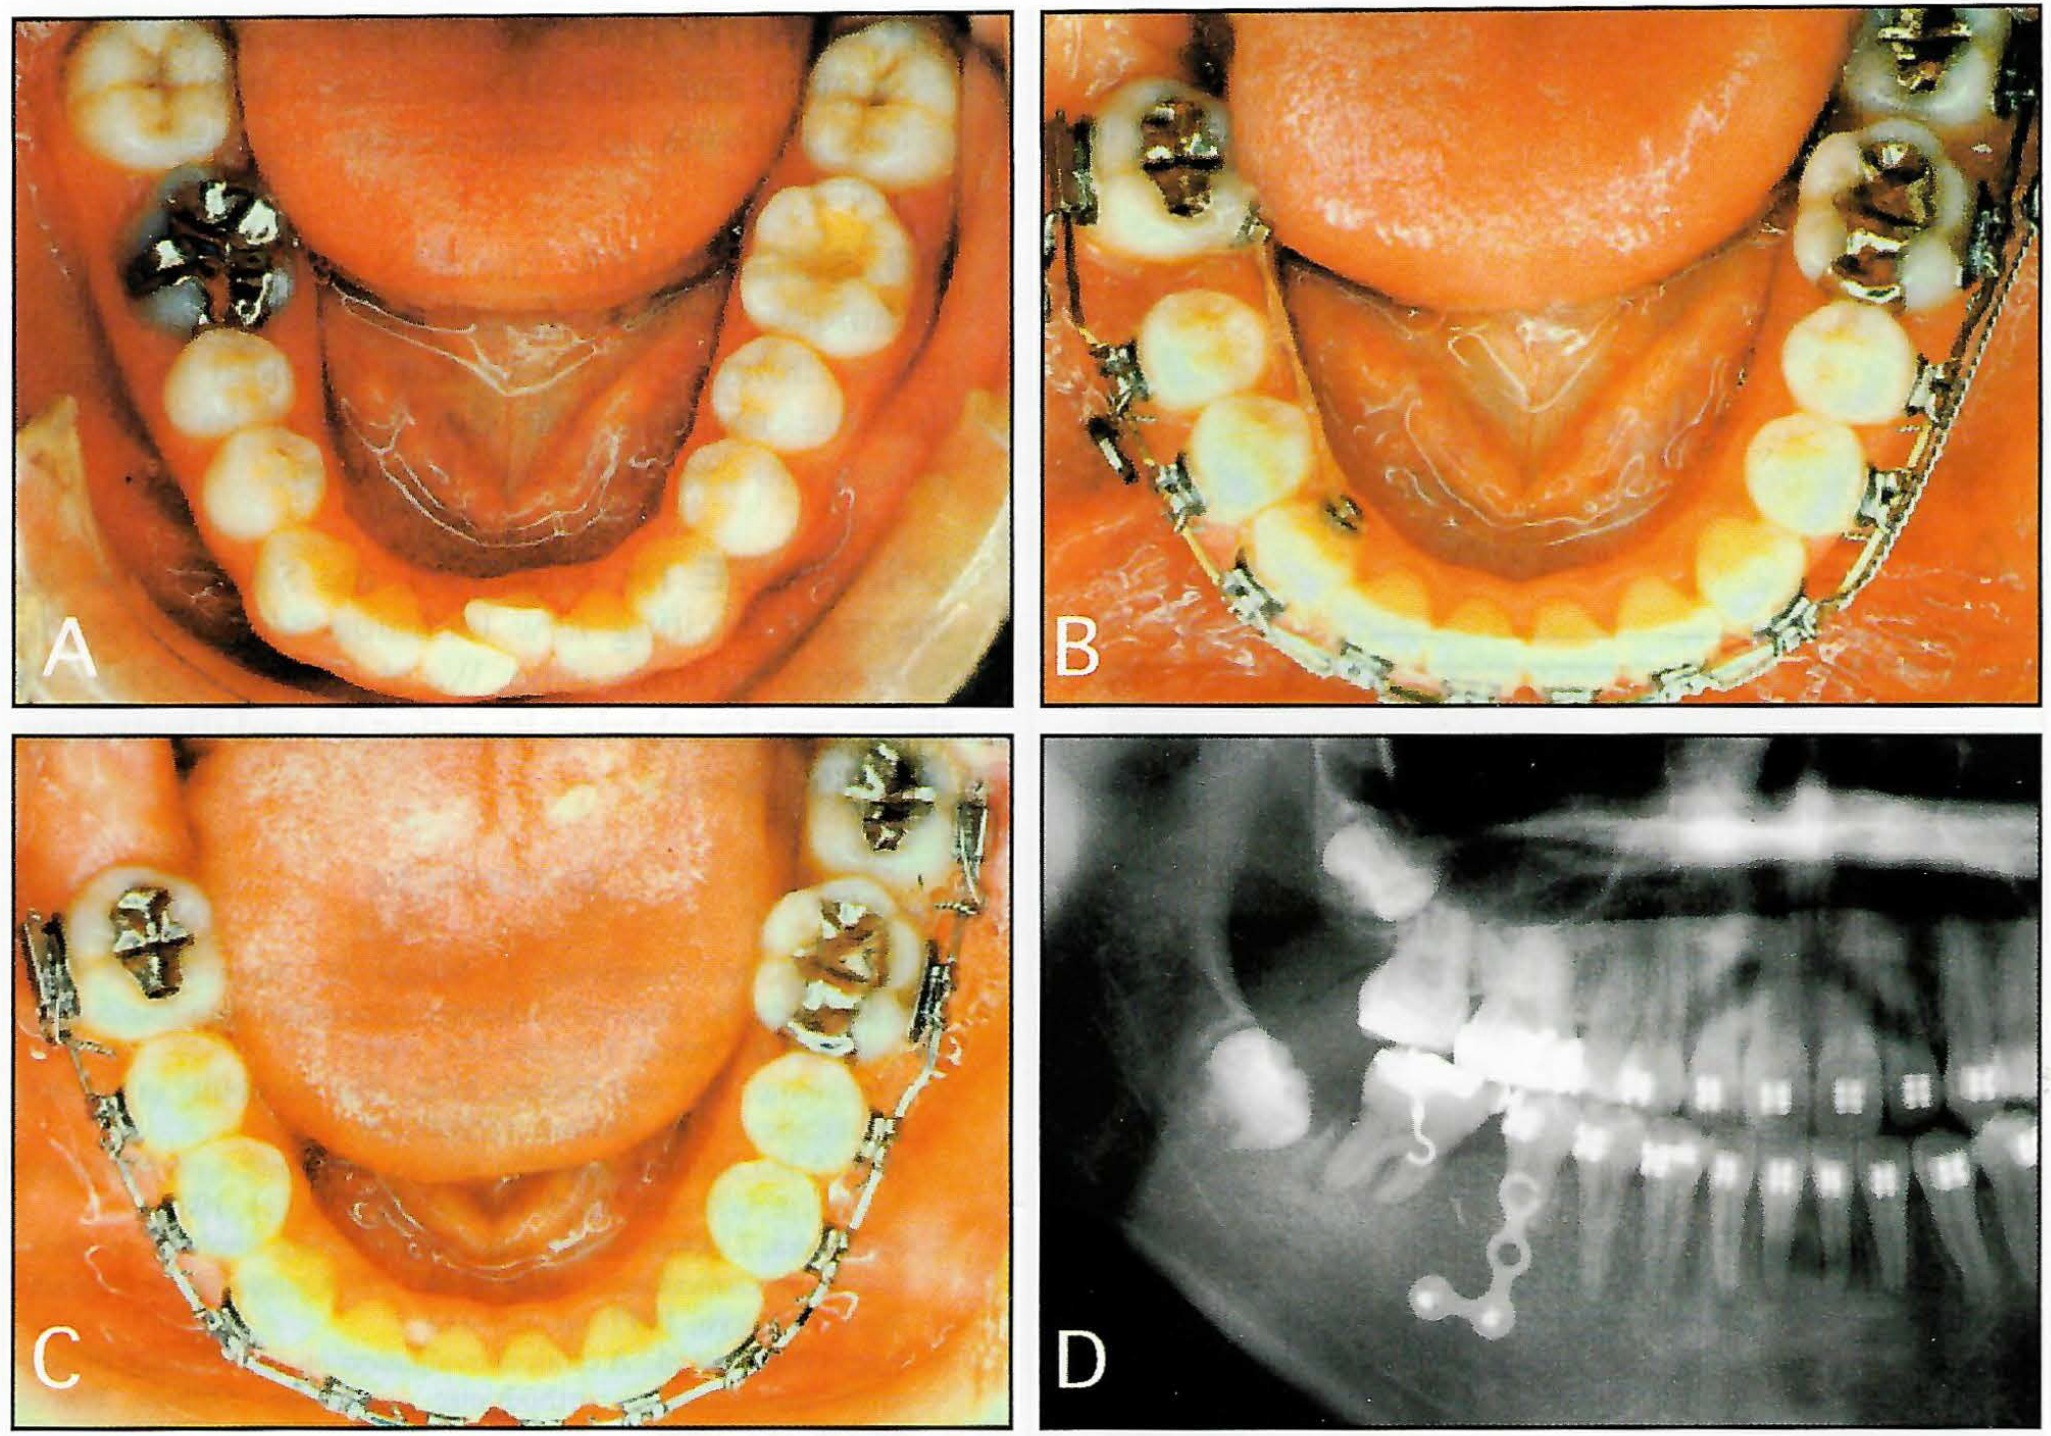

DR. SUGAWARA In 1992, we had a patient with a severe anterior crossbite and no molars for anchorage in the mandibular dentition (Fig. 1). She had an average-size mandible, so orthognathic surgery was not an option. We decided to apply an anchorage system that we had read about and was similar to dental implants. Her alveolar bone was not thick enough to contain permanent implants. We didn't know which of two systems would be the more comfortable for the patient, so we used a simple titanium screw on one side and a titanium miniplate on the other.

Fig. 1 First SAS patient (1992). A. Before treatment. B. Three years after debonding. C. Panoramic x-ray taken during treatment, with titanium screw on patient's right and titanium miniplate on patient's left.